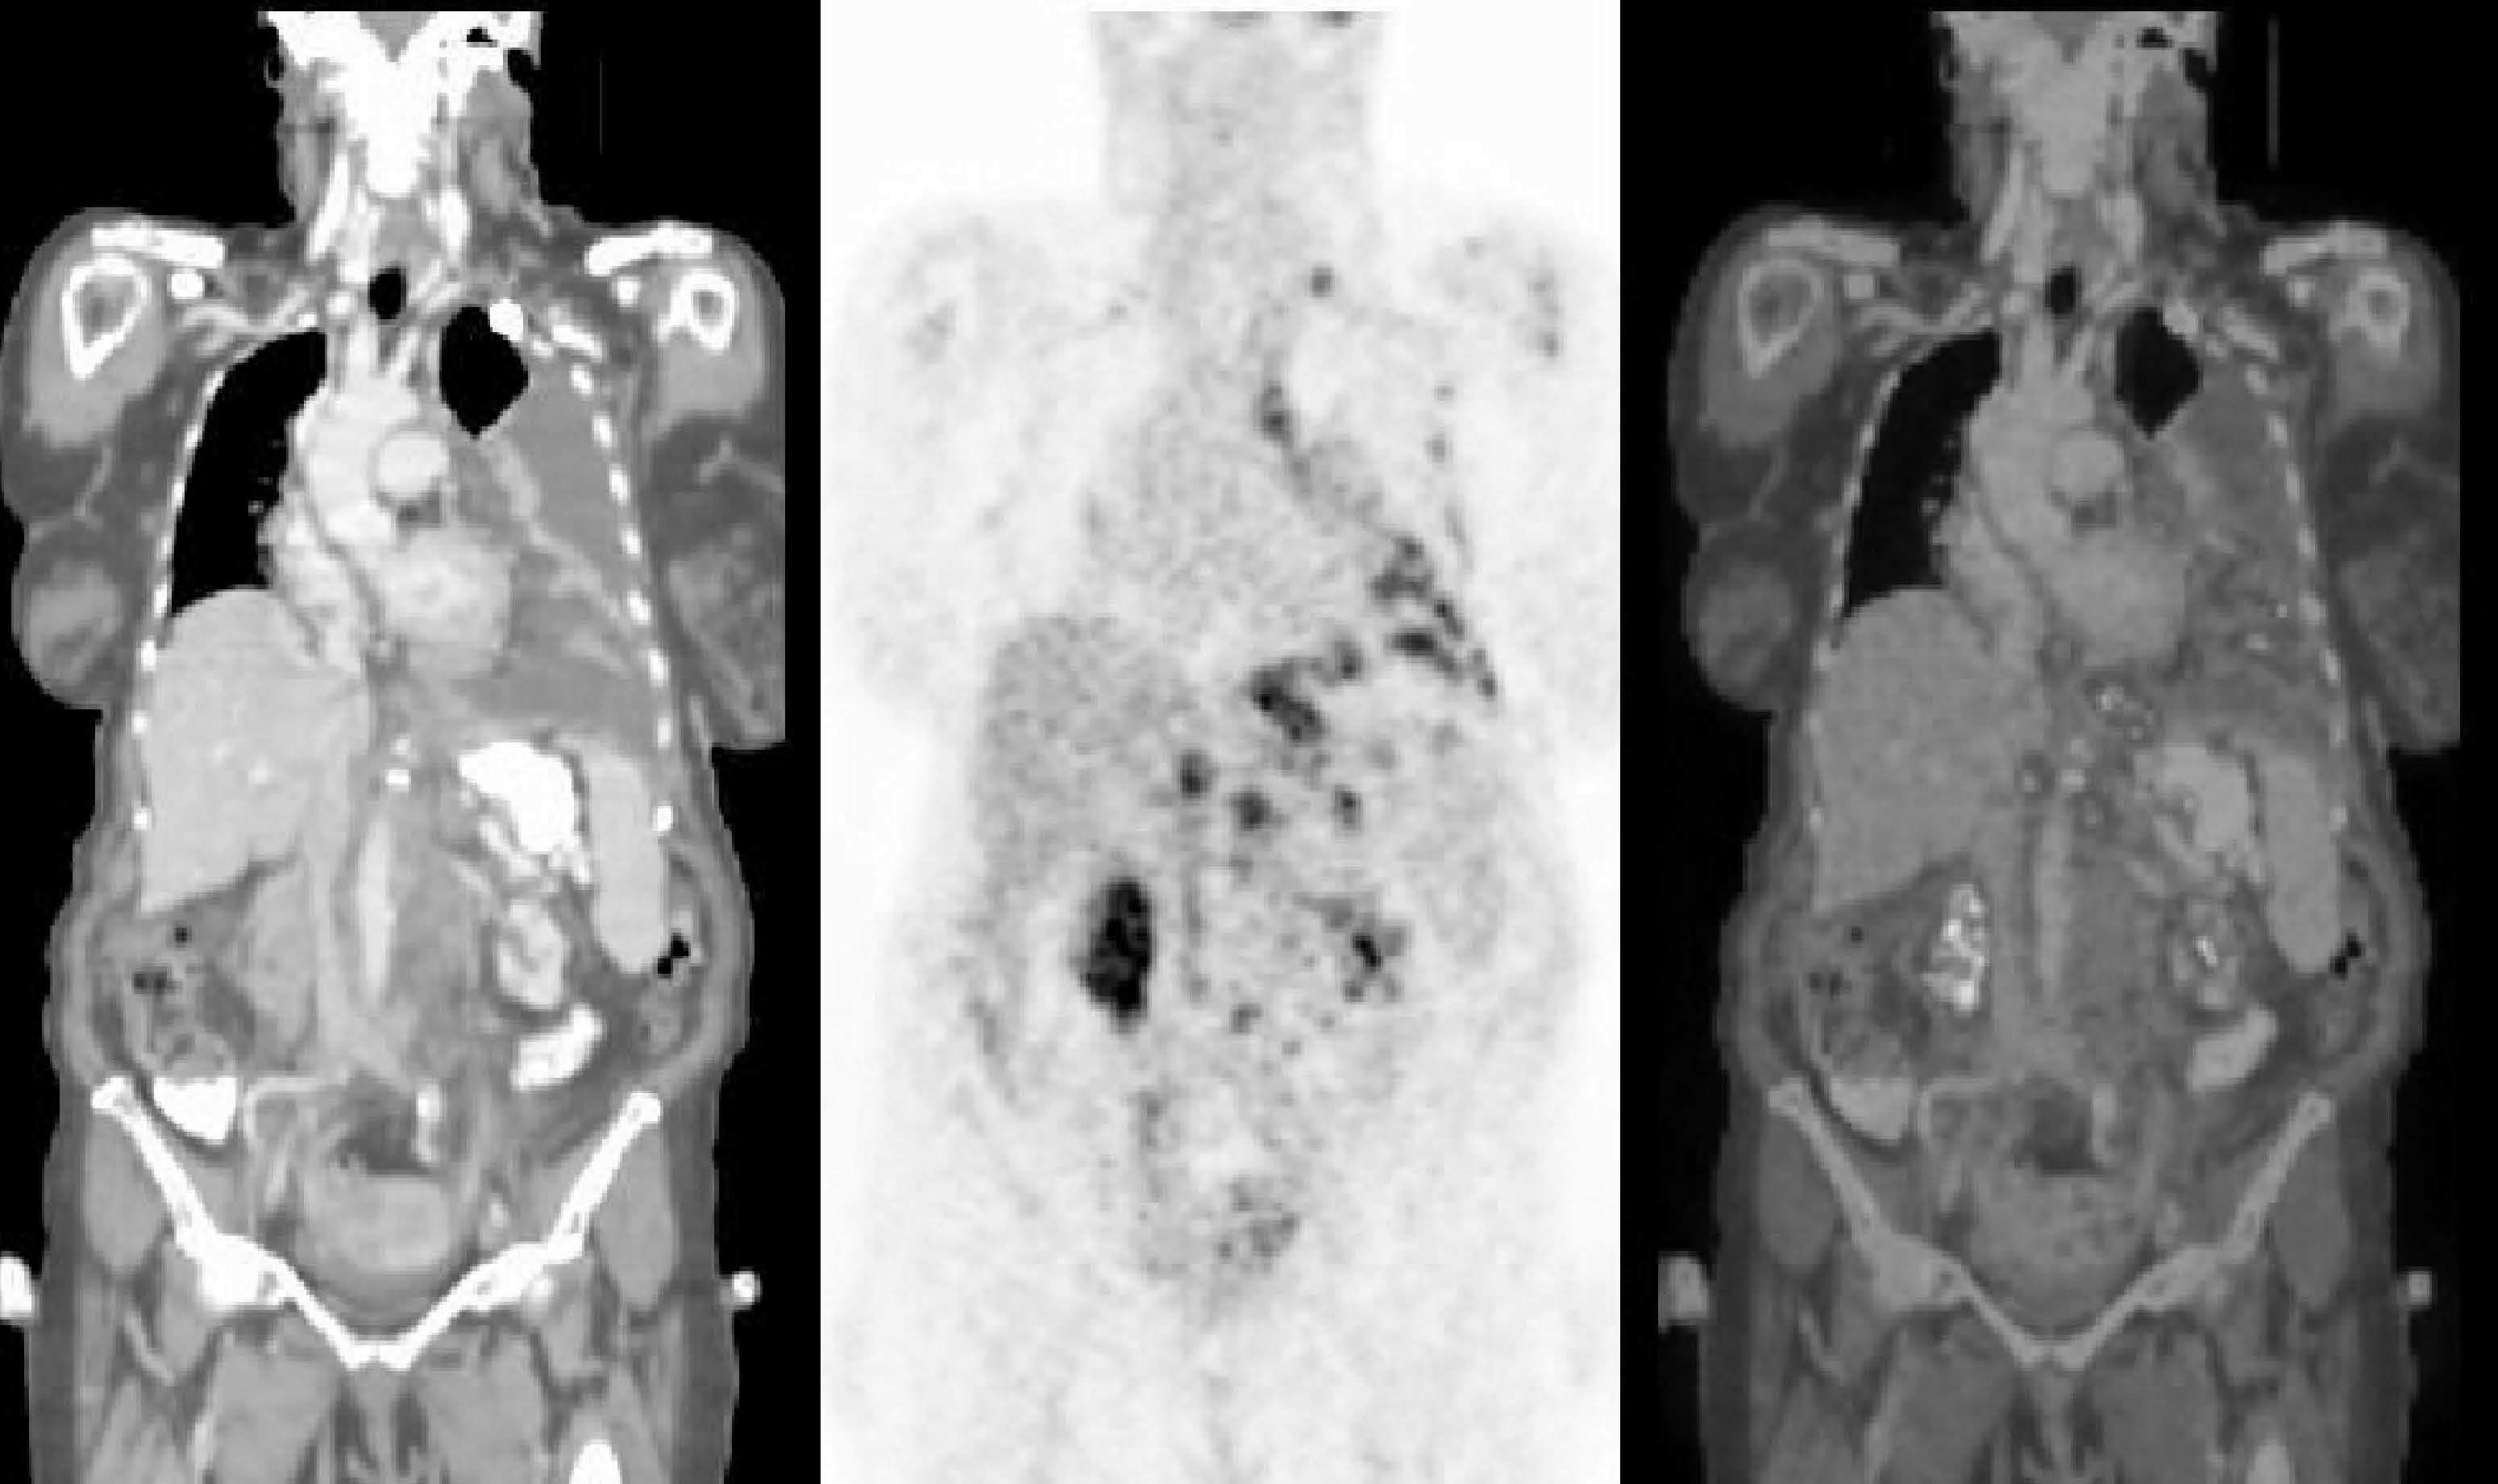

Fig. 5.--Estudio con tomografía por emisión de positrones-tomografía computarizada (PET/TC) de estadificación en Linfoma no Hodgkin (LNH). Mujer de 65 años con el diagnóstico inicial de LNH de alto grado. El estudio se realizó con los brazos a lo largo del cuerpo por las condiciones clínicas de la paciente, que no toleró la posición de brazos por encima de la cabeza. La PET (B) presenta incremento de 18FDG en localización supra e infradiafragmática. La TC (A) y la fusión PET/ TC (C) muestran la afectación en cadena supraclavicular izquierda, mediastino, pleura y cadenas ganglionares paraórticas bilaterales.